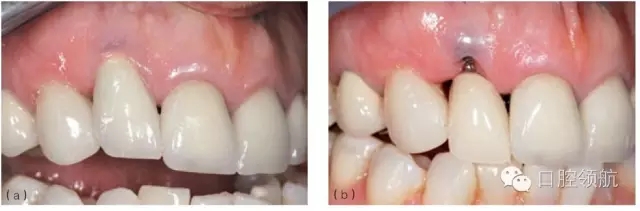

圖8.25 (a)右上頜側(cè)切牙(7號(hào)位點(diǎn))種植體唇側(cè)黏膜退縮。種植體有唇側(cè)植入位置不佳。(b)拆下冠和基臺(tái)并以暫時(shí)的局部義齒修復(fù)后的臨床情況。局部義齒選取正確的冠長(zhǎng)度,顯示出軟組織垂直向缺損。(c) 牙合面觀:拆下冠和基臺(tái),安裝愈合基臺(tái)。清楚可見(jiàn)種植體唇側(cè)植入位置不佳。(d)做頰側(cè)全厚瓣翻瓣,可見(jiàn)牙槽嵴骨水平與種植體相對(duì)關(guān)系算是常規(guī)位置。(e)從腭側(cè)獲取結(jié)締組織瓣,覆蓋種植體唇側(cè)與牙合面。(f)唇面觀:瓣關(guān)閉縫合后,暫時(shí)局部義齒修復(fù)。(g)術(shù)后2個(gè)月,結(jié)締組織移植瓣已完全與周圍組織融合,種植體完全覆蓋。(h)牙槽嵴頂做小切口暴露種植體頂端,安裝一個(gè)選磨過(guò)的愈合基臺(tái)。(i)種植體粘結(jié)暫時(shí)冠。原來(lái)退縮的程度有所減小,但是完全恢復(fù)軟組織的高度沒(méi)有實(shí)現(xiàn)。種植體唇側(cè)植入位置不佳時(shí),恢復(fù)的軟組織垂直高度有限。